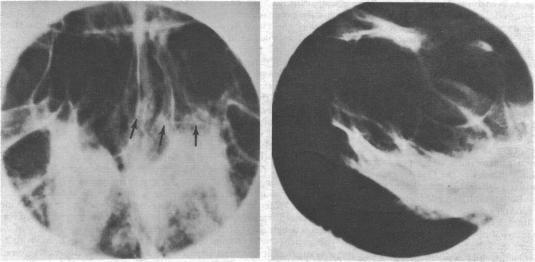

Seventeen term pregnancies occurred in 14 amenorrhoeic women with hyperprolactinaemia and radiological evidence of pituitary tumour. The abortion rate was high (32%). All but one of the term pregnancies occurred after ovulation-inducing treatment with human gonadotrophins and bromocriptine (four and 12 pregnancies respectively). Two of the 14 women had visual complications during pregnancy, but neither had serious residual visual impairment. Two patients had possible pituitary enlargement during pregnancy.Bromocriptine may be the most suitable primary treatment for many infertile women with prolactin-secreting tumours. Tumour complications during pregnancy are a definite risk, but most pregnancies went uneventfully to term. Patients with pituitary tumour should be carefully evaluated before starting ovulation-inducing treatment with bromocriptine alone, and they should be told of the possible risks and of the advantages and disadvantages of pretreatment with irradiation or surgery. Patients should be carefully monitored during pregnancy and have their visual fields checked frequently. If visual complications due to tumour enlargement occur during a pregnancy, reinstituting bromocriptine may be the treatment of choice. If this fails, other forms of treatment such as induction of labour, high-dose corticosteroid treatment, pituitary implantation of yttrium-90, or surgery may be effective.

14名闭经且患有高泌乳素血症并有垂体瘤影像学证据的女性发生了17次足月妊娠。流产率很高(32%)。除1例足月妊娠外,其余均发生在使用人促性腺激素和溴隐亭诱导排卵治疗后(分别为4次和12次妊娠)。14名女性中有2名在孕期出现视力并发症,但均无严重的残余视力损害。2例患者在孕期可能出现垂体增大。溴隐亭可能是许多患有泌乳素分泌性肿瘤的不孕女性最合适的初始治疗方法。孕期肿瘤并发症确实存在风险,但大多数妊娠顺利至足月。在开始单独使用溴隐亭诱导排卵治疗前,应对垂体瘤患者进行仔细评估,并告知她们可能的风险以及放疗或手术预处理的利弊。孕期应仔细监测患者,并经常检查其视野。如果孕期因肿瘤增大出现视力并发症,重新使用溴隐亭可能是首选治疗方法。如果无效,其他治疗方法如引产、大剂量皮质类固醇治疗、垂体植入钇-90或手术可能有效。